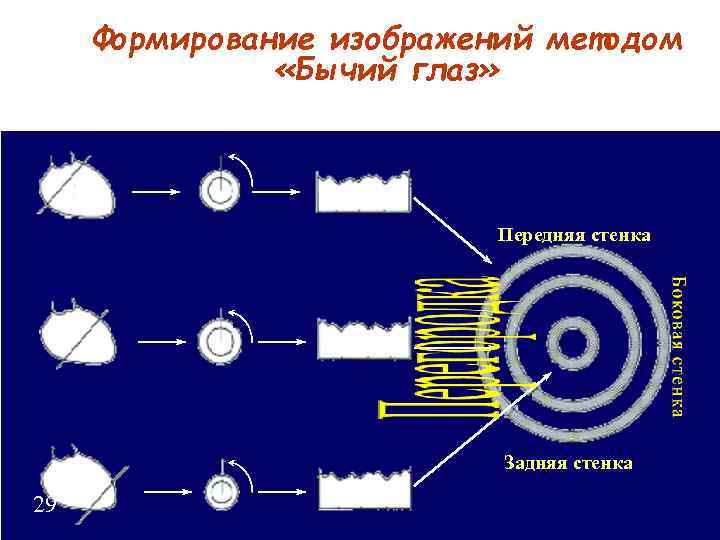

Формирование изображений методом «Бычий глаз» Передняя стенка Задняя стенка 29

Формирование изображений методом «Бычий глаз» Передняя стенка Задняя стенка 29